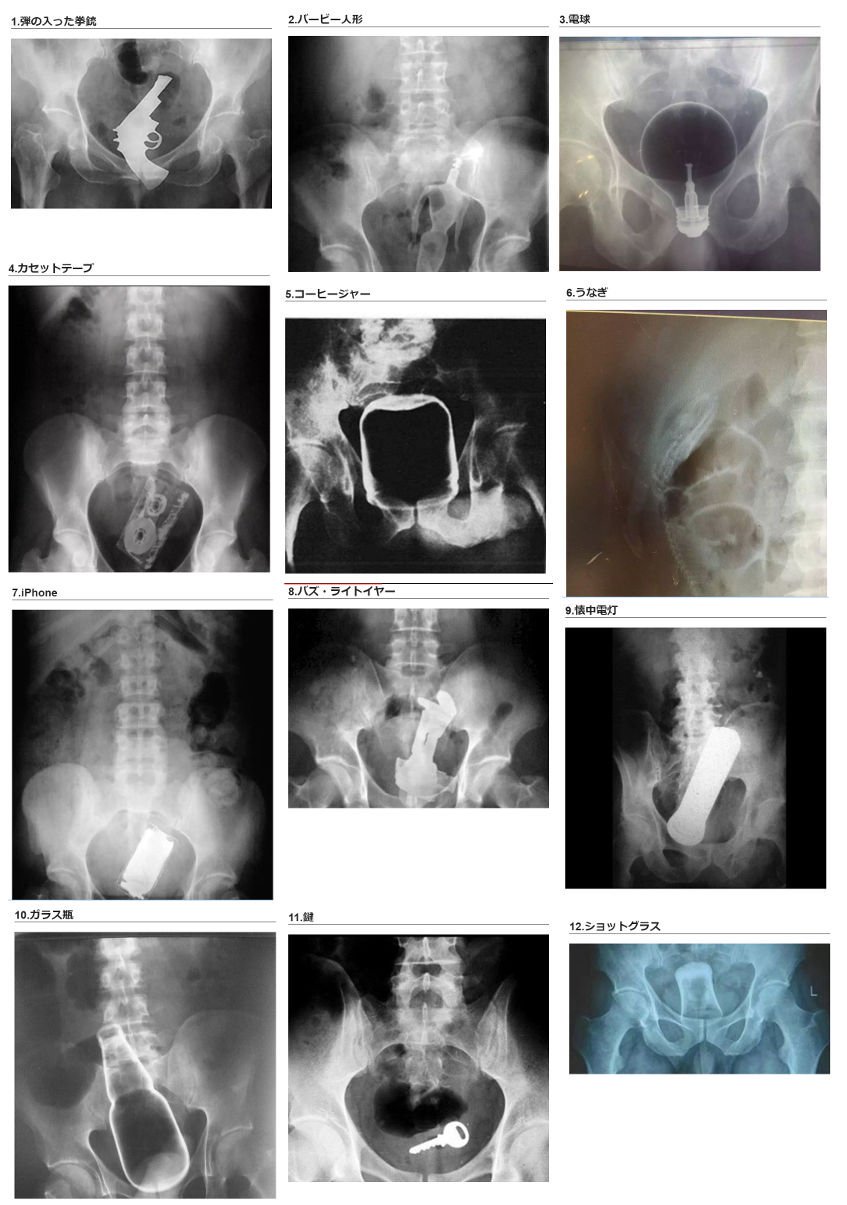

そしてバズ・ライトイヤーで駄目だった>>781

あと人のケツなんて汚ねー所に突っ込まれたうなぎくん可哀想酷すぎる流れで駄目だった…